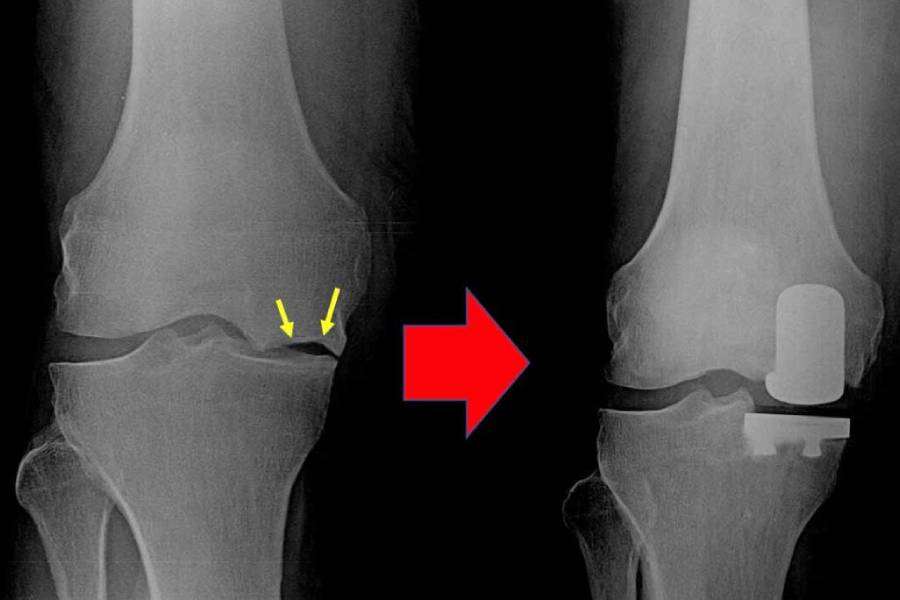

Knee joint replacement is one of the most frequently performed orthopaedic surgeries. It replaces the worn-out surfaces of the knee with metal and plastic components, providing pain relief and stability.